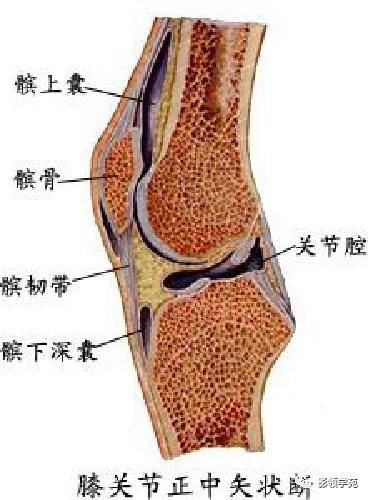

关节与韧带系统

关节与韧带系统